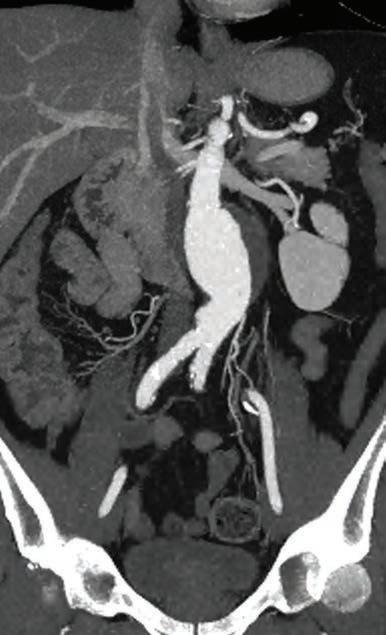

Medical Forum spoke with the Perkins Institute’s Associate Professor Juliana Hamzah and vascular surgeon and Head of Department of Vascular and Endovascular Surgery at Sir Charles Gairdner Hospital Professor Shirley Jansen, about what could be the biggest advance in the treatment of atherosclerosis since the invention of statins at the end of the 1970s – and one that potentially dwarfs them –the very real chance of a cure.

A cure for peripheral artery disease?

continued from Page 17

About half of patients with symptomatic PAD require lower extremity revascularisation (such as bypass surgery, angioplasty with stent insertion, or atherectomy or thrombectomy) during their lifetimes, either electively to treat symptoms of severe claudication, or to save limbs in patients presenting with acute limb ischemia or CLTI.

“But counterintuitively perhaps, revascularisation does not improve overall vascular prognosis, as it does not address the underlying vascular risk. Indeed, there is an even greater risk for MACEs or MALEs in patients who have undergone revascularisation,” Dr Jansen said.

“We have patented a drug, developed here at the Harry Perkins Institute that is a reconstructed fusion protein, two proteins joined together, consisting of a biologic agent and ligand that has specific recognition to a receptor that is aberrantly expressed in lipidenriched cells (foam cells) in the arterial wall.

“Hence, this agent, once it enters the blood circulation, targets and accumulates in the arterial wall where lipid deposits and plaques are located.

“That chemical sensor is the key to targeting this drug effectively. It accumulates very well with an excellent biodistribution profile in plaque relative to normal healthy tissue. It congregates on those areas where it is needs to be, and that is exactly what we engineered it to do.

“We know by looking at Professor Jansen’s patient samples from surgery where patients have had plaques removed from their carotid arteries to prevent stroke, all of them seem to show recognition of this drug in lipid-rich regions.

“The original protein is actually naturally produced in our body. When we have a disease, this protein is produced in a high amount and acts on multiple cell types. We reprogram it differently to produce an exclusive effect on lipid-loaded cells, without toxicity. “Its action is highly reproducible throughout the entire arterial system, including the small vessels, and we now know how our drug triggers the cell to metabolise the lipids.”

Professor Hamzah explained that because this novel treatment works by breaking down the chemistry of the lipid itself, using its own processes to do so, the drug effect is specific to plaques.

The drug is currently undergoing regulatory requirements for approval and commercialisation, but once it is ready for release, both women believe that it could revolutionise treatment for PAD globally.

“Of course, the ideal scenario would be for humans not to get PAD in the first place. However, for those patients who progress despite risk factor management and healthy living, this drug could be an option,” Professor Jansen said.

“There's no reason to think that this could not be a GP prescribed drug, though it will definitely be in the domain of specialists to begin with.”

“The challenging part of bringing a new drug to market is convincing funding bodies that you have a strong contender,” Professor Hamzah explained.

“Even though this is a potential blockbuster, it was tough to convince ourselves and then other people that it was possible to safely and effectively dissolve atherosclerotic plaques. It took us 10 years to replicate the pre-clinical studies that work each time. Only now, I feel more convinced that it's not a fluke or chance.

“It's not completely 100% guaranteed, but it's a ‘first in class’ situation, there is nothing else to compare it with.

“We still have challenges ahead with the human protein – such as, how conserved is the effect of the drug in a human? So that’s our focus now.”

“All the medical management and procedures we have for PAD and CLTI are good, but they are not curative,” Prof. Jansen concluded. “We're thinking about applying the word cure to a pathology that has never had the concept applied to it. And, if it continues to prove itself, that will mean a dramatic difference to millions of people.”